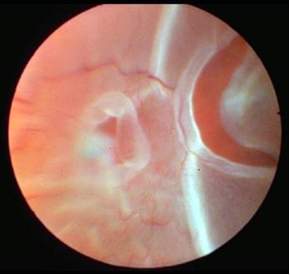

dio vidnog polja. Odljubljena retina se vidi kao jedna sivoružičasta poluprovidna

membrana preko koje prelaze retinalni krvni sudovi i koja pri pokretu

oka podrhtava (slika 2). Ukoliko vrijeme prolazi, dolazi do gliozne proliferacije,

tako da odljubljena retina više nije providna i dobija sivkastu boju.

Slika 2